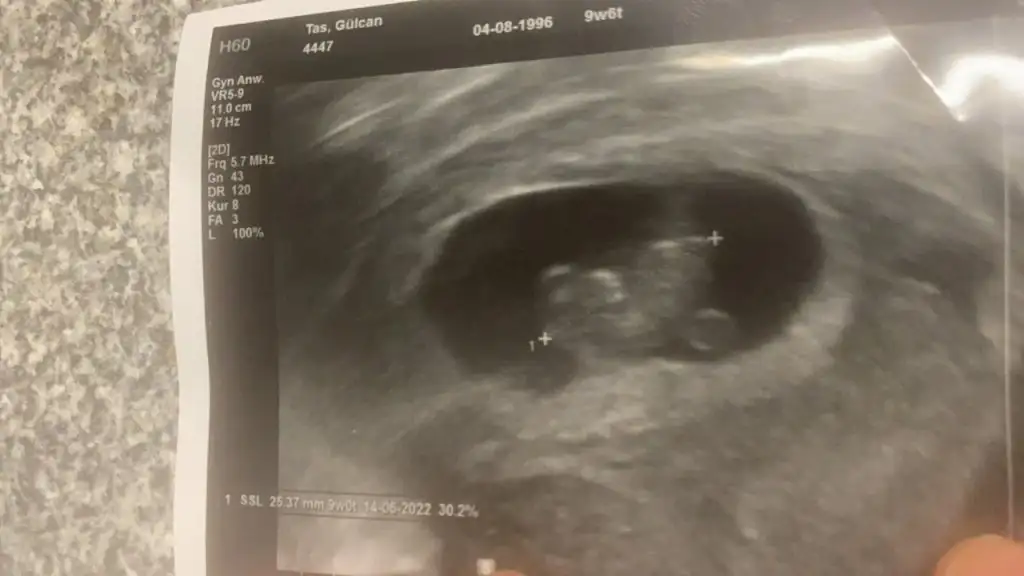

Canım banada bi el atsana bakalım ne olacak tahminin soldaki 6+1 sağdaki 7+6hangisini beğenirsen🤭